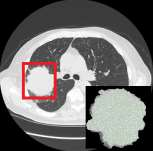

The elasticity of soft tissues has been widely considered as a characteristic property to differentiate between healthy and vicious tissues and, therefore, motivated several elasticity imaging modalities, such as Ultrasound Elastography, Magnetic Resonance Elastography, and Optical Coherence Elastography. This paper proposes an alternative approach of modeling the elasticity using Computed Tomography (CT) imaging modality for model-based feature extraction machine learning (ML) differentiation of lesions. The model describes a dynamic non-rigid (or elastic) deformation in differential manifold to mimic the soft tissues elasticity under wave fluctuation in vivo. Based on the model, three local deformation invariants are constructed by two tensors defined by the first and second order derivatives from the CT images and used to generate elastic feature maps after normalization via a novel signal suppression method. The model-based elastic image features are extracted from the feature maps and fed to machine learning to perform lesion classifications. Two pathologically proven image datasets of colon polyps (44 malignant and 43 benign) and lung nodules (46 malignant and 20 benign) were used to evaluate the proposed model-based lesion classification. The outcomes of this modeling approach reached the score of area under the curve of the receiver operating characteristics of 94.2 % for the polyps and 87.4 % for the nodules, resulting in an average gain of 5 % to 30 % over ten existing state-of-the-art lesion classification methods. The gains by modeling tissue elasticity for ML differentiation of lesions are striking, indicating the great potential of exploring the modeling strategy to other tissue properties for ML differentiation of lesions.